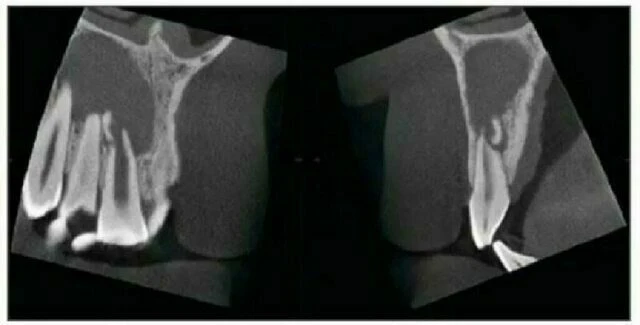

Trường hợp nội tiêu